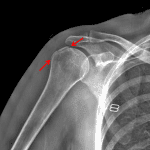

Age: 55

Sex: Female

Indication: Shoulder pain

- Acute minimally displaced fracture of the greater tuberosity

- Mild degenerative changes of the acromioclavicular joint

- Right cervical carotid artery calcification

- Greater tuberosity fracture

Acute minimally displaced fracture of the greater tuberosity.

No joint malalignment.

Mild degenerative changes of the acromioclavicular joint. Glenohumeral joint space is maintained.

Right cervical carotid artery calcification.